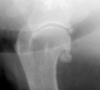

What is seen in these radiographs?

solid periosteal reaction